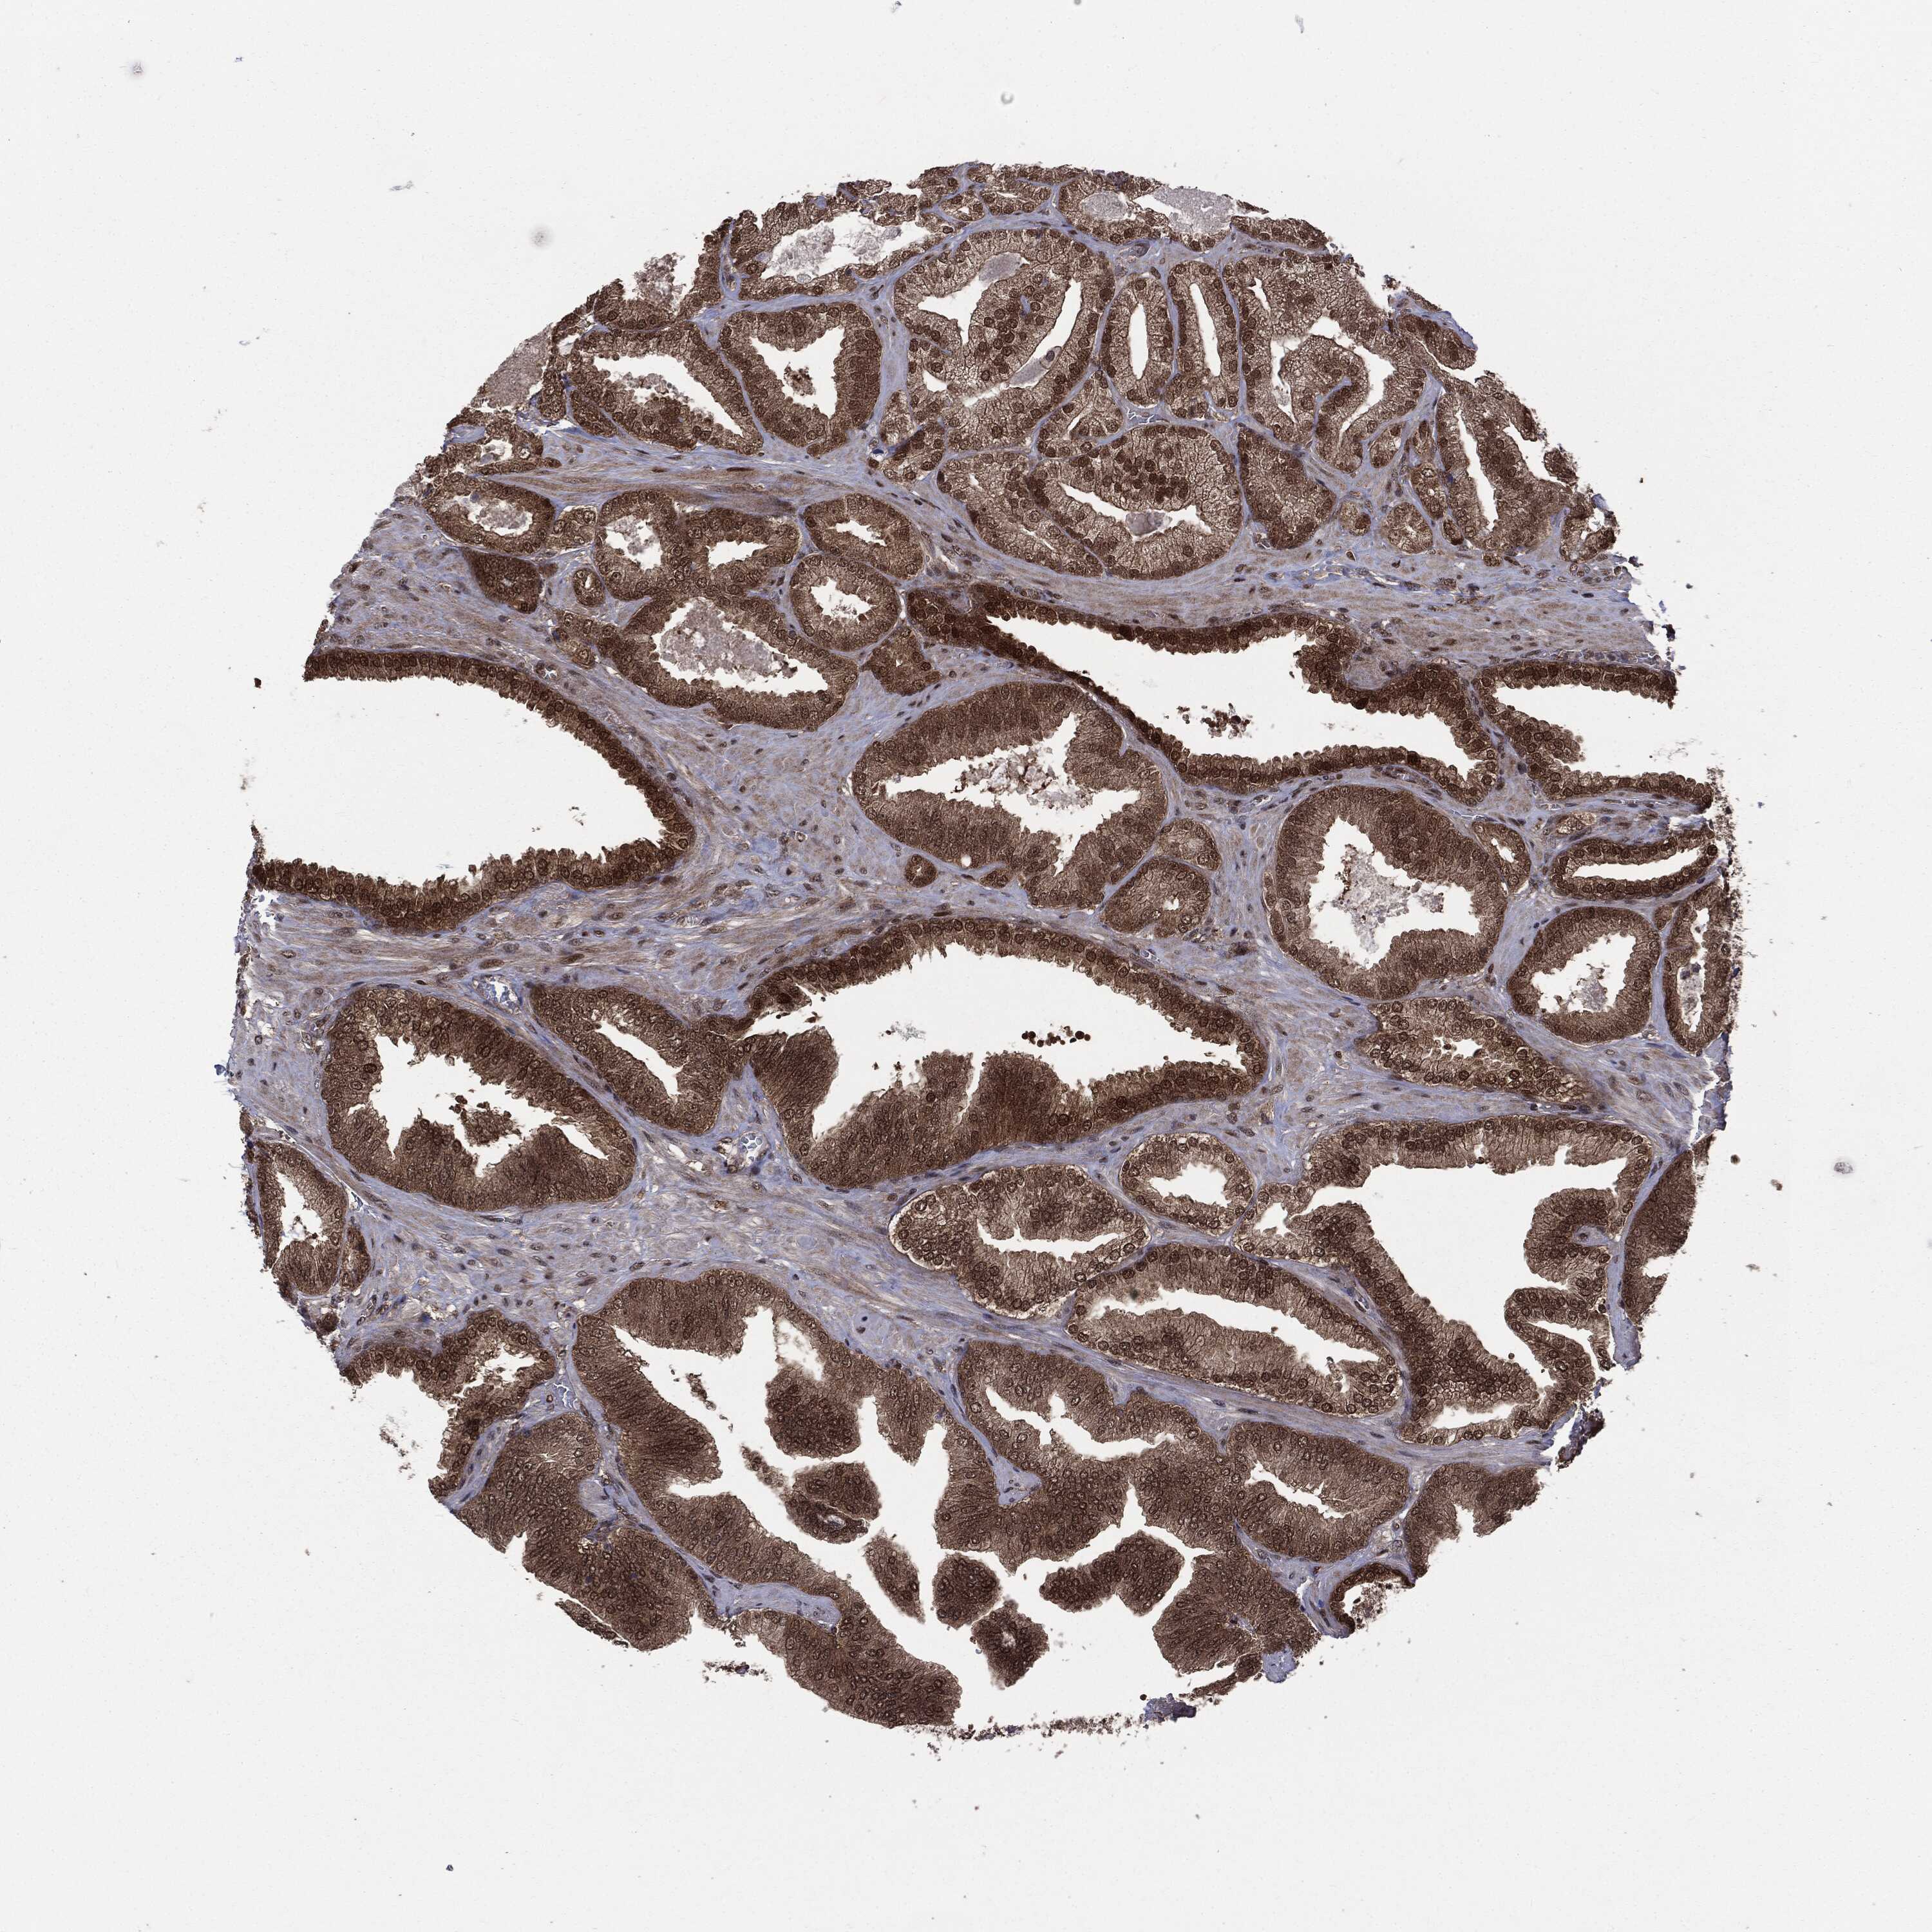

PROSTATE CANCER - Protein expressioni

A mouse-over function shows sample information and annotation data. Click on an image to view it in a full screen mode. Samples can be filtered based on level of antibody staining by selecting one or several of the following categories: high, medium, low and not detected. The assay and annotation is described here.

Note that samples used for immunohistochemistry by the Human Protein Atlas do not correspond to samples in the TCGA dataset.

Antibody stainingi

Antibody staining in the annotated cell types in the current human tissue is reported as not detected, low, medium, or high, based on conventional immunohistochemistry profiling in selected tissues. This score is based on the combination of the staining intensity and fraction of stained cells.

Each image is clickable and will lead to virtual microscopy that enables deeper exploration of all samples and also displays staining intensity scores, fraction scores and subcellular localization as well as patient and tissue information for each sample.

Adenocarcinoma, Low grade

Adenocarcinoma, High grade

Adenocarcinoma, NOS

Adenocarcinoma, Medium grade